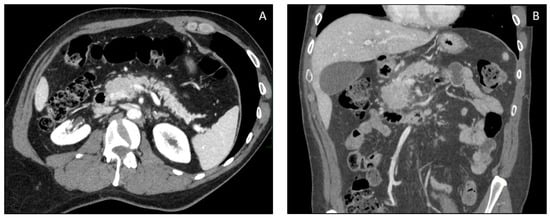

2.3. Diagnosis and Imaging

| CT Findings | Description |

Bowel wall thickening

| Mucosal hyperemia |

| Mesenteric vessel engorgement |

| Distended colon, fluid filled and air-fluid levels |

| Pericolic fat stranding |